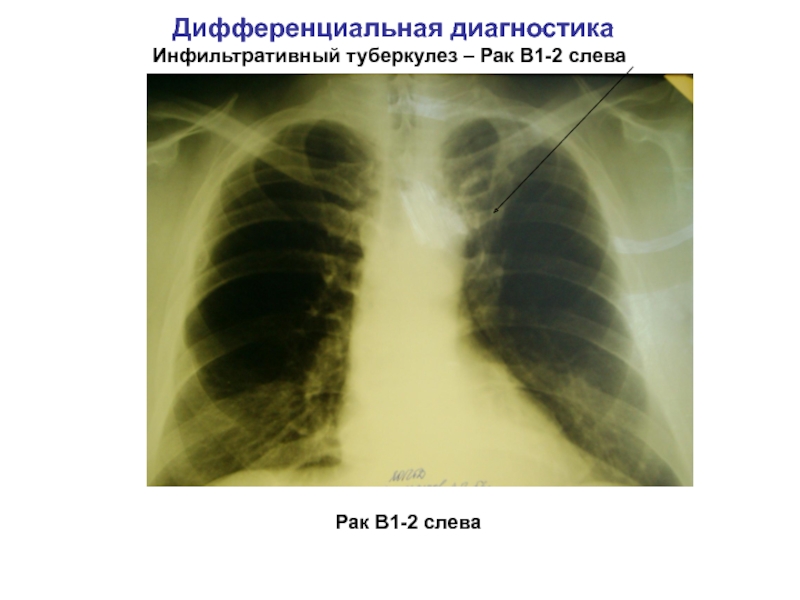

Очаговый и инфильтративный туберкулез презентация - 94 фото